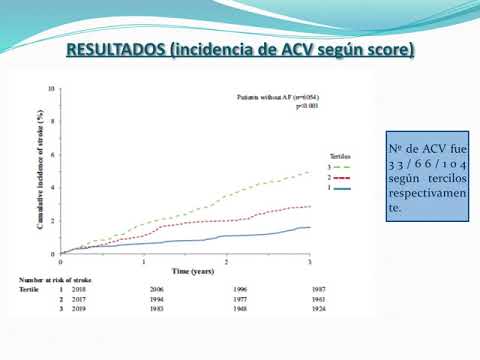

Riesgo de ACV en pacientes con ICC sin FA. Dr. Sebastián Ayuso. Residencia de Cardiología. Hospital C. Argerich. Buenos Aires

Riesgo de ACV en la Insuficiencia cardíaca crónica. Dr. Sebastián Ayuso. Residencia de Cardiología. Hospital C. Argerich. Buenos Aires